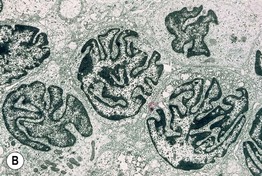

• Defined historically by the triad of (1) erythroderma; (2) generalized lymphadenopathy; and (3) the presence of neoplastic T cells (Sézary cells) in the skin, lymph nodes, and peripheral blood (Fig. 98.7).

Fig. 98.7 Sézary syndrome. A Diffuse erythroderma is present. B Electron photomicrograph of a skin biopsy showing characteristic Sézary cells. Courtesy, Rein Willemze, MD.